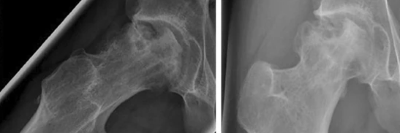

Vorgehen bei Hüftkopfnekrosen in der pädiatrischen Unfallchirurgie

Die posttraumatische Hüftkopfnekrose stellt die schwerwiegendste Komplikation nach einer Schenkelhalsfraktur dar. Bei Kindern und Jugendlichen steht der Erhalt des Hüftgelenks im Vordergrund. Eine allgemeingültige Empfehlung fehlt, verschiedene Maßnahmen stehen zur Debatte. Erlaubt es die Anatomie, bietet die Endoprothese eine geeignete Therapieoption.

Bildnachweise

Lagerungsplagiozephalus/© Aus Linz et al. Positional Skull Deformities Etiology, Prevention, Diagnosis, andTreatment, mit freundlicher Genehmigung © Deutscher Arzte-Verlag GmbH, Röntgen eines Ellenbogens mit Humerusfraktur/© Sampaio E et al. / all rights reserved Springer Medizin Verlag GmbH, Hüftkopfnekrose eines 13-Jährigen /© Loose O et al. / all rights reserved Springer Medizin Verlag GmbH, Röntgen einer Beckenfraktur und Abdomen-CT bei Jugendlichem/© Karvouniaris N. et al. / all rights reserved Springer Medizin Verlag GmbH, Ausgeprägte fluktuierende okzipitale Schwellung am Kopf eines Babys nach Geburtstrauma/© Härtel C et al. / all rights reserved Springer Medizin Verlag GmbH, Rückenuntersuchung bei kleinem Mädchen/© Viacheslav Lakobchuk / stock.adobe.com (Symbolbild mit Fotomodellen), Schreiendes Baby/© AzmanL / Getty Images / iStock (Symbolbild mit Fotomodell), Gebrochener Arm eines Kindes erhält Gips/© Rafael Ben-Ari / stock.adobe.com (Symbolbild mit Fotomodellen), Kind mit Unterarmfraktur/© DragonImages / stock.adobe.com (Symbolbild mit Fotomodellen), Kind mit Gipsarm/© nycshooter / Getty Images / iStock (Symbolbild mit Fotomodell), Antikörper - Molekül /© luismmolina / Getty Images / iStock (Symbolbild), Adoleszente idiopathische Skoliose/© Springer Medizin Verlag GmbH, Hämatom an der Stirn des 9-Jährigen/© Dr. med. Thomas Hoppen, Morbus Perthes rechts bei 5-jährigem Jungen/© Gemeinschaftsklinikum Mittelrhein, Operative Behandlung des Torticollis muscularis congenitus/© Ploeger M et al. / all rights reserved Springer Medizin Verlag GmbH, Morbus Osgood-Schlatter/© Springer Medizin, Search Icon, Arthropedia, Frau unkenntlich fasst sich ans Knie/© Pornpak Khunatorn / Getty Images / iStock (Symbolbild mit Fotomodell), Ärzteteam führt Hüftoperation durch/© ATRPhoto / stock.adobe.com (Symbolbild mit Fotomodell), Gebrochener Fuß im Gips/© Aleksandr Kirillov / stock.adobe.com (Symbolbild mit Fotomodell)